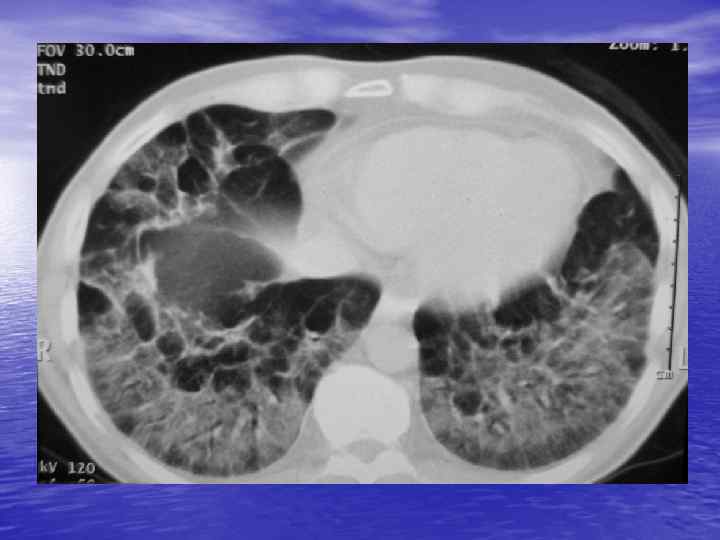

Преимущества спиральной КТ: ü Возможность проведения исследования с болюсным ü ü ü ü ü контрастированием Высокая разрешающая способность; Высокая скорость исследования; Получение высококачественных изображений костных структур; Возможность обследования всего тела; Возможность проведения исследования больных под наркозом; Возможность детальной оценки состояния крупных и периферических сосудов в условиях искусственного контрастирования; Высокая информативность метода при черепномозговых травмах в остром периоде; Ранняя диагностика ишемических и геморрагических инсультов; Метод выбора для диагностики заболеваний легких; Планирование лучевой терапии.